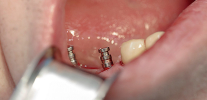

Ecco alcune procedure necessarie:

- Presa delle impronte dopo il posizionamento dell'impianto, la fabbricazione e il fissaggio di una protesi temporanea (per non rimanere senza denti per quasi un anno e mezzo);

- Dopo l'attecchimento dell'impianto riuscito - ripetuto incisione gengivalecoprendo il moncone sull'impianto, rimuovendo il moncone e fissando il moncone di guarigione (eseguito 2-3 settimane prima dell'installazione di una protesi permanente). La prima gengiva consente di regolare la posizione della mucosa molle attorno alla futura corona;

- Rimozione del precedente gengivale e sostituzione con un moncone (un elemento che funge da base per la protesi), installandolo sul moncone e inserendo una protesi permanente realizzata prima delle calotte.

Le manipolazioni elencate sono già incluse nel costo dell'impianto. Ma i monconi meritano un'attenzione particolare: questi sono gli elementi che collegano la parte intraosseo dell'impianto e la corona.